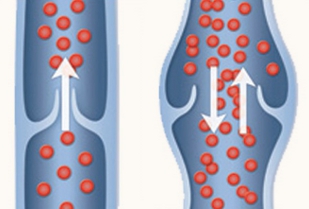

Vene varicose degli arti inferiori: diagnosi e trattamento

Evidence 2013;5(9): e1000055

Vene varicose degli arti inferiori: diagnosi e trattamento

Evidence 2013;5(9): e1000055